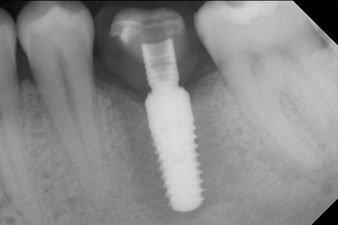

radiografía de control

Figura 10: La radiografía de control muestra que se había producido una correcta osteointegración y que la corona se había atornillado sin dejar hendiduras.